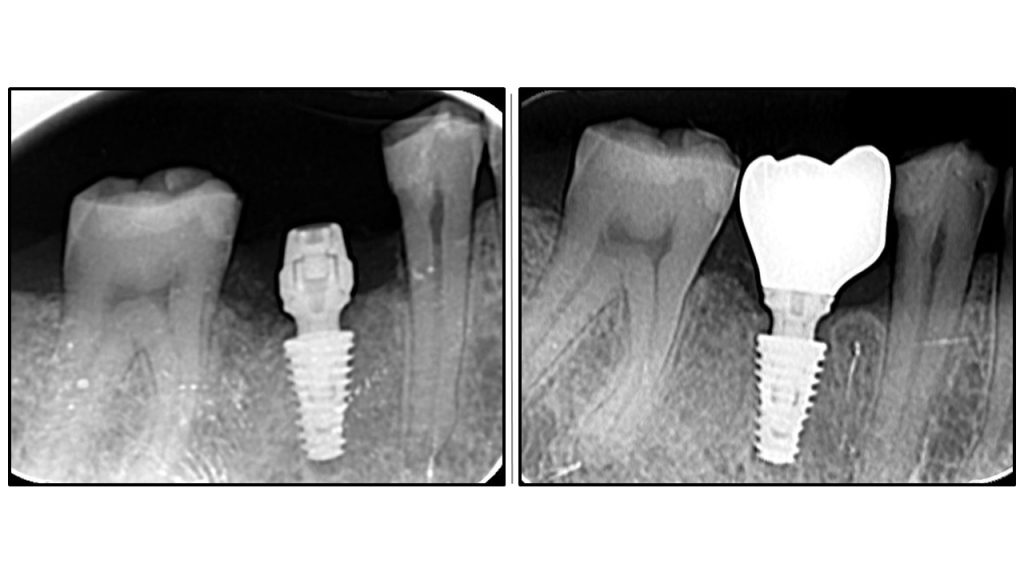

Radiographic Analysis: Crestal Bone Stability

Comparative radiographic study of crestal bone stability: OAOT protocol. Postoperative radiography vs. Final prosthetics.

The first image showing postoperative radiography and the second final ceramic crown

Bone remodelling

Bone remodelling around implant abutment connection is flawless

Stable peri implant tissue

No bone recession is visible

OAOT protocol - superior results.